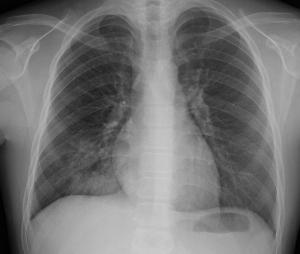

마이코플라즈마 폐렴(Mycoplasma pneumoniae)은 작은 박테리아인 마이코플라즈마에 의해 발생하는 폐렴의 한 형태입니다. 이 박테리아는 폐렴뿐만 아니라 기관지염과 같은 다양한 호흡기 감염을 일으킬 수 있습니다.

더 심각한 경우에는 호흡 곤란이나 가슴 통증이 발생할 수 있으며, 폐렴이 더 심각한 단계로 진행되고 있음을 나타낼 수 있습니다. 이는 즉각적인 의료적 조치가 필요한 상황입니다.